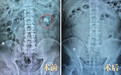

12年里,陈先生因左肾结石,先后在外院做过两次取石手术,未能“断根”。此后结石如野草滋生——左肾铸型结石,2.8×2.0公分,如鹿角般紧紧攀附在肾盂肾盏;更棘手的是,周围还密布着大大小小的继发结石,肾功能已出现不可逆损伤。

凭借这一招牌技术组合,常立高教授成功将陈先生左肾多发结石,清除得干干净净。他表示,这一技术能在更微创伤的前提下,最大程度保护肾脏,真正实现“取石”与“护肾”双赢。